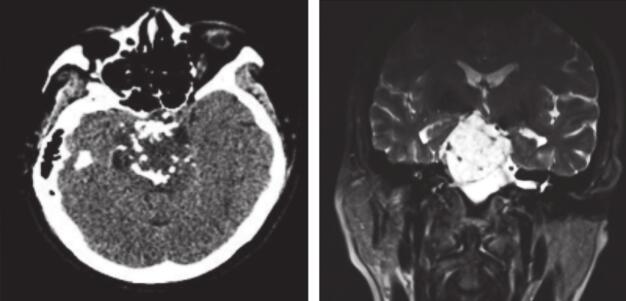

患者术后病理回报:(右中颅底)高分化软骨肉瘤。患者外科病房出院后就诊放疗中心行放疗,予6MV X线局部野IMRT放疗DT:54.75Gy/26Fx(图2),病程中予对症支持治疗。患者放疗前后(图3、图4)病灶缩小。患者随访至2017年8月,病灶稳定,症状同前。

图2 患者术后放疗计划示意图